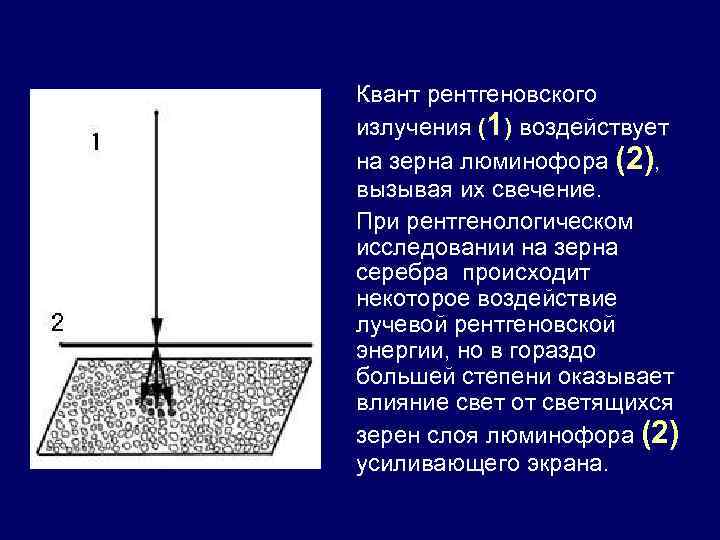

Квант рентгеновского излучения (1) воздействует на зерна люминофора (2), вызывая их свечение. При рентгенологическом исследовании на зерна серебра происходит некоторое воздействие лучевой рентгеновской энергии, но в гораздо большей степени оказывает влияние свет от светящихся зерен слоя люминофора (2) усиливающего экрана.